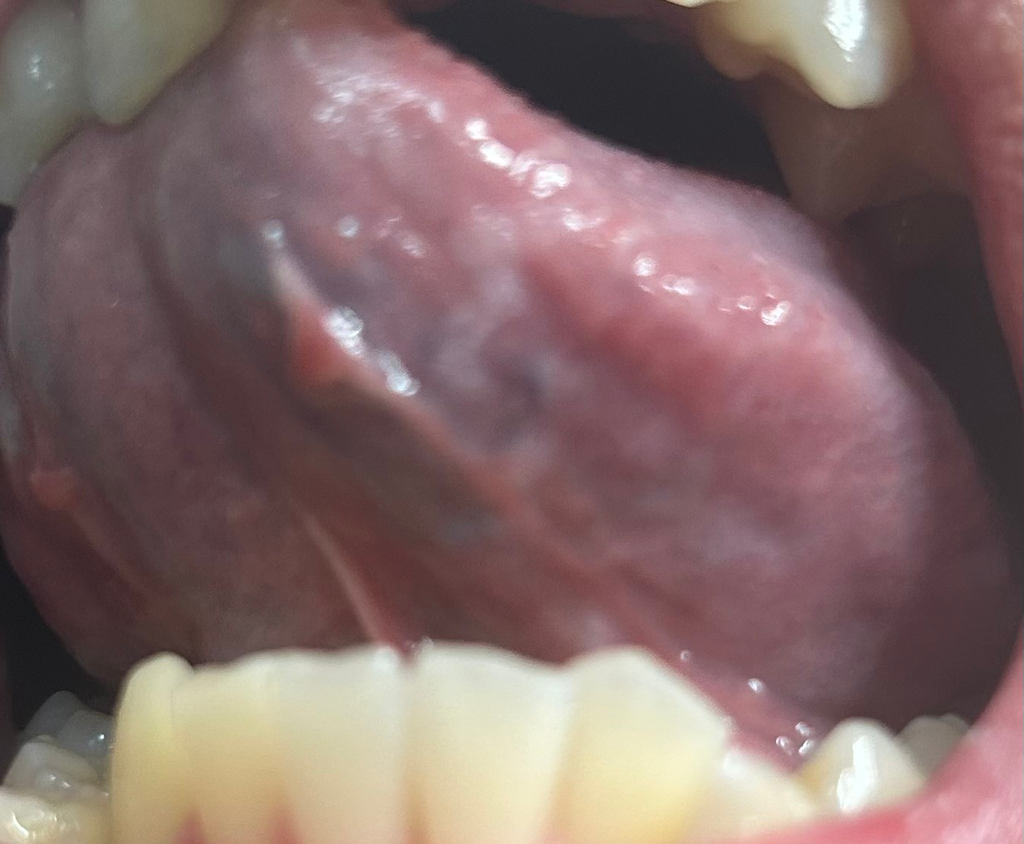

일단 구강암은 아닌것으로 보입니다.

구강과 혀 전반에 걸쳐 퍼져있는 병소가 만약에 암이라면 이미 말기암 일것임으로 말이 되지 않습니다.

거의 정상으로 보입니다만.

단수히 물집이 잡히신거 같습니다. 크게 문제가 잇는건 아니니 너무 걱정하지않으셔도 될것같습니다. 구내염증상이신거 같습니다 .

구강내 점막은 자극을 받거나 하면 점막에 변화가 생기기도 합니다.

구강암의 가능성은 매우 작지만 걱정이 되신다면 치과엣 진료를 받아 보는것이 좋습니다.